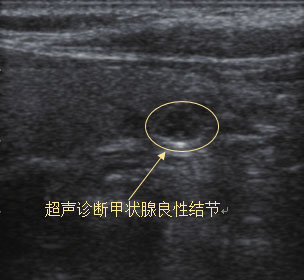

一旦确诊甲状腺结节,我们普通人最担心的问题就是这个结节是不是癌。事实上,尽管临床上甲状腺结节的检出率很高,但是只有5%的甲状腺结节是甲状腺癌。判断甲状腺结节的良恶性有多种方式,其中最常用也是首选的是甲状腺超声检查。很多病人也是因为超声检查发现了结节,再进一步做其他检查明确诊断的。

甲状腺超声报告怎么看?

结节的大小并不是判断良恶性的标准,主要还是结合超声检查报告中的描述,若包含以下几点,提示恶性的可能性就比较大:①微小钙化(砂砾状钙化、针尖样或簇状分布的钙化等);②边缘不规则(边界模糊/微分叶);③纵横比>1;④实质性、低回声或极低回声结节;⑤结节内或周边血流丰富(TSH正常情况下);⑥有颈部淋巴结异常等。

对于普通人来说,通过描述不太容易判断结节的性质,如果超声报告上同时打有TI-RADS分类,那么我们可以从这个分类判断结节的性质。TI-RADS分类(见下表)按0~6类对甲状腺结节进行分类,如果分级在4类以上,说明恶性可能性大,需要及时与医生沟通。